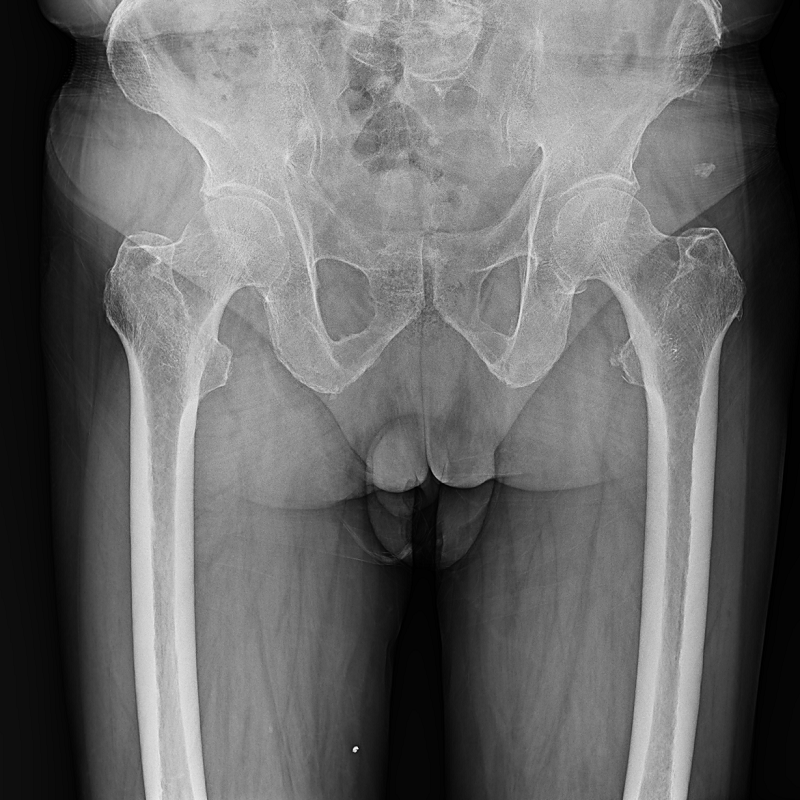

● 圖像拼接

系統(tǒng)可以識(shí)別曝光圖像,無需設(shè)置識(shí)別點(diǎn)即完成精準(zhǔn)拼接,呈現(xiàn)大范圍完整影像。